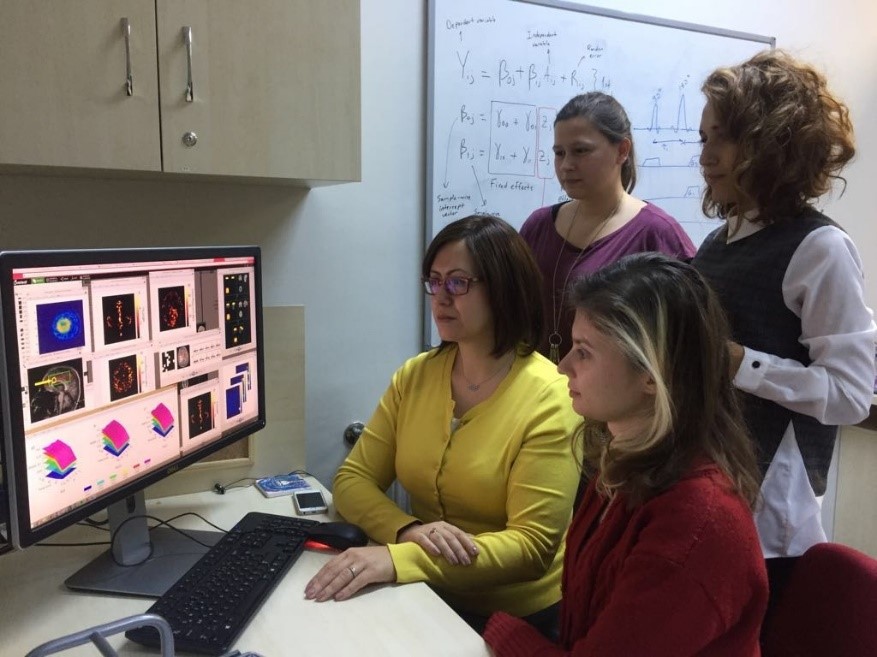

Institute of Biomedical Engineering

- Computational Imaging Laboratory

https://bme.bogazici.edu.tr/en/computational-imaging-laboratory

Field of Study: Magnetic resonance imaging techniques (MR spectroscopic imaging (MRSI), arterial spindle labelling (ASL), diffusion tensor imaging (DTI), etc.) are used to identify anatomical, physiological and biochemical changes due to brain diseases, classification of medical image data for disease diagnosis using machine learning and deep learning methods, and image enhancement (super enhancement).To identify anatomical, physiological and biochemical changes due to brain diseases using magnetic resonance imaging techniques (MRI), classification of medical image data for disease diagnosis using machine learning and deep learning methods and image enhancement (super resolution), to accelerate routine MRSG techniques used in the clinic, To develop quantitative molecular MR imaging techniques for more sensitive and accurate data acquisition and processing, to develop modelling and analysis methods to create MR parametric maps, to develop user-friendly data analysis interfaces, and to produce phantoms that mimic brain chemistry and anomalies.